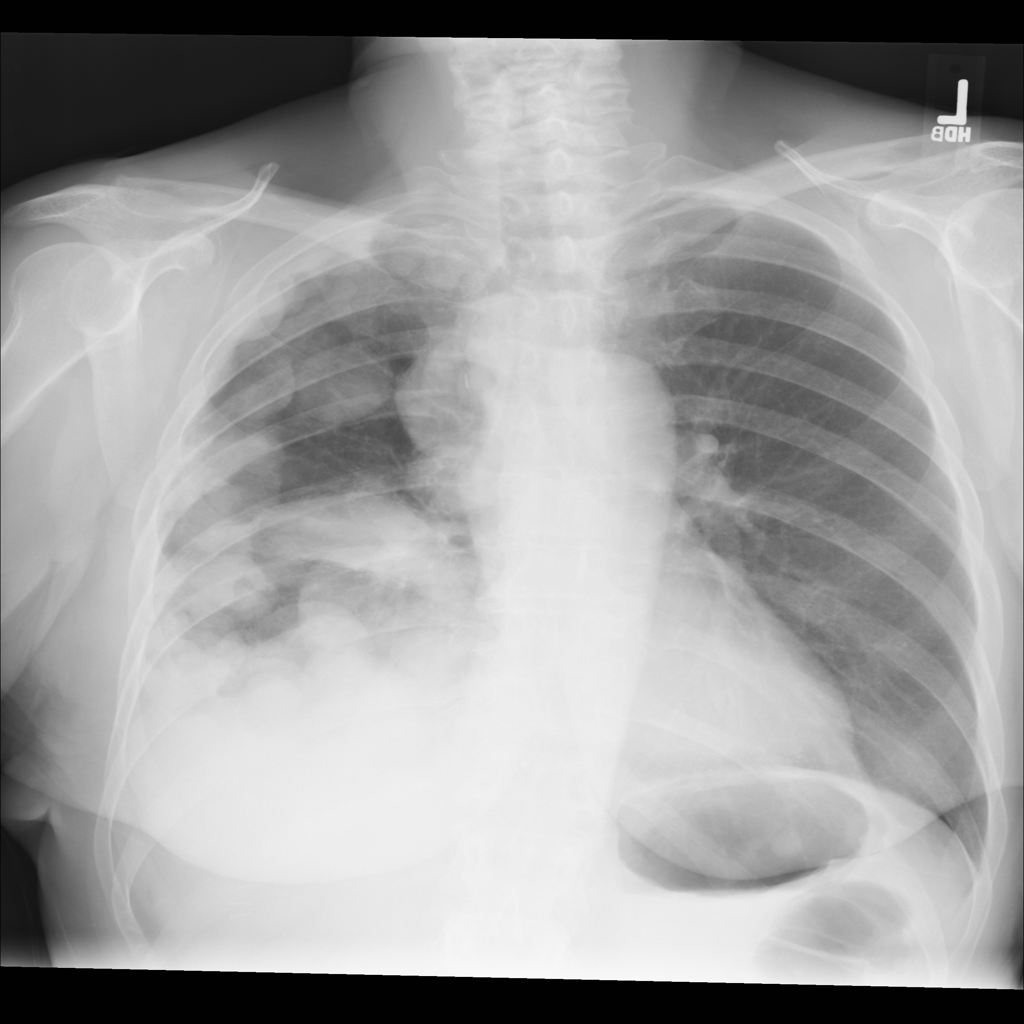

Mass

A mass is a larger focal opacity or lesion seen on the image. It is a descriptive finding that can have several causes and usually needs more imaging or clinical context to characterize.

PAT-4639 · IMG-024Mass

PAT-4639 · IMG-024

AP